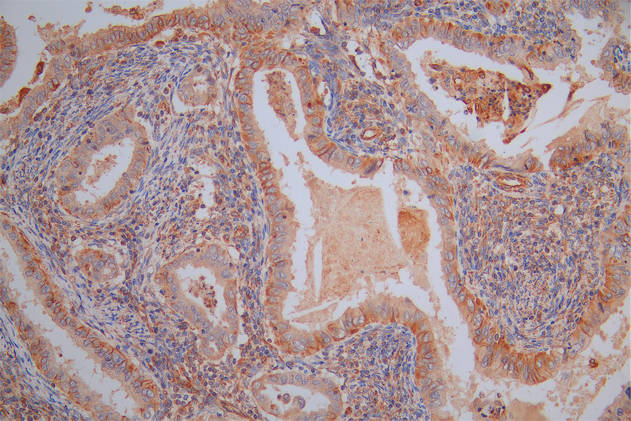

Immunohistochemistry analysis of human colon cancer using CSB-PA10599A0Rb at dilution of 1:100